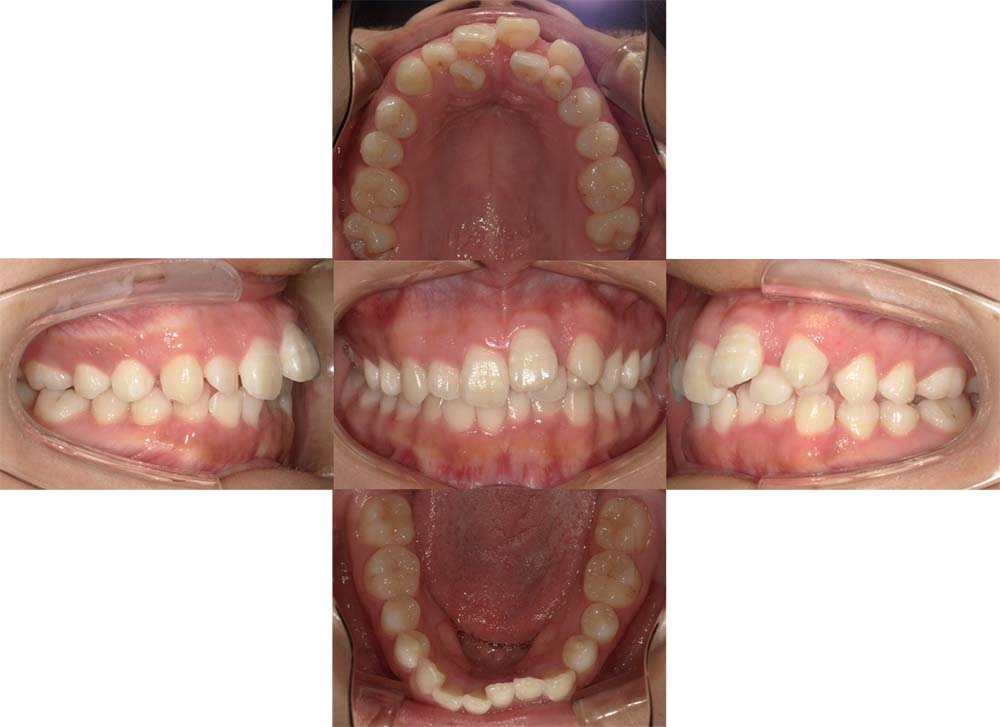

症例04

| 主訴 | 歯並びのガタガタと出っ歯が気になる。 |

| 診断名あるいは主な症状 | 上顎前突、叢生 |

| 年齢/性別 | 16歳・女性 |

| 矯正ステージ | 大人の矯正治療 |

| 治療方法 | ワイヤー矯正 |

| 抜歯部位/抜歯有無 | 抜歯 |

| 治療内容 | 抜歯したスペースを使用し、ガタガタの改善と上下顎前歯を後退させた。 |

| 費用 |

85万円程度(2025.10時点の料金となります。) ※矯正基本料金、審美ブラケットを含む |

| 治療期間 | 2年5ヶ月 |

| 主なリスク・副作用 | 痛み、歯根吸収、歯肉退縮、虫歯、後戻り |